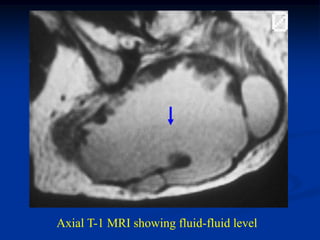

Case #1174

Axial T-1 MRI showing fluid-fluid level

Case #1174 78 yearfemale with large hematoma in buttock area looking like a hemorrhage into an MFH T-2 MRI showing fluid-fluid level

Axial T-1 MRIshowing fluid-fluid level